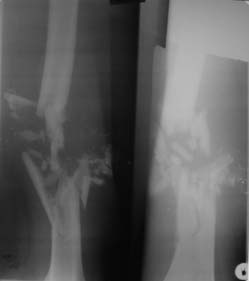

На рентгенограмме правой бедренной кости 02.11.2011г. определяется оскольчатый перелом средней трети ее. В мягких тканях множественные мелкие инородные тела металлической плотности менее 1-го миллиметра в диаметре – «металлическая пыль».

На рентгенограмме правой бедренной кости определяется оскольчатый перелом средней трети ее без значительного смещения отломков. В мягких тканях множественные мелкие инородные тела металлической плотности менее 1-го миллиметра в диаметре – «металлическая пыль» (снимки переданы в в/ч 26826).